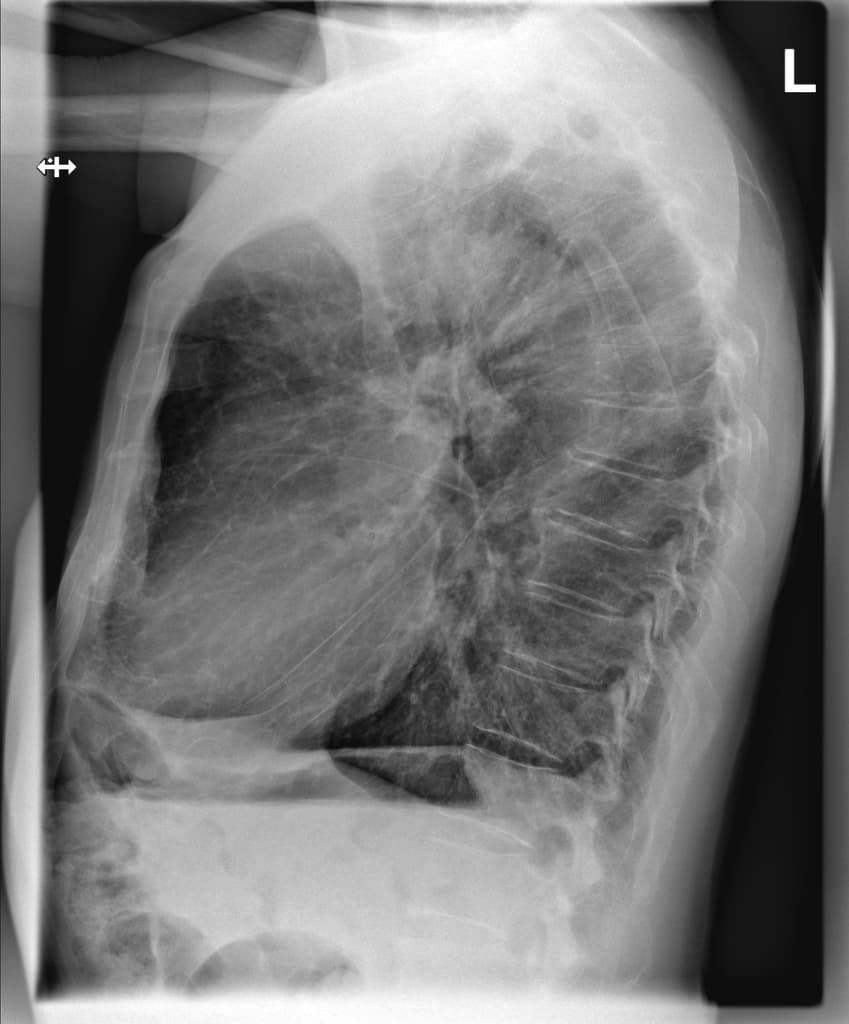

Phân suất tống máu giảm nhẹ (EF ~45%) trên siêu âm tim trong khám sức khỏe định kỳ hàng năm. Tiền sử tăng huyết áp và tiền sử gia đình bị bệnh động mạch vành.

Hình ảnh cộng hưởng từ cho thấy viêm cơ tim mức độ nhẹ, kèm phù cơ tim nhẹ và các dấu hiệu tổn thương cơ tim không do thiếu máu cục bộ (non-ischemic myocardial injury) ở một bệnh nhân có phân suất tống máu giảm nhẹ được phát hiện trong khám sức khỏe định kỳ hàng năm dành cho phi công. Trong thời gian nằm viện ngắn, chẩn đoán suy tim với phân suất tống máu giảm nhẹ (heart failure with mildly reduced ejection fraction – HFmrEF) đã được xác lập. Các nguyên nhân như bệnh động mạch vành, bệnh van tim và rối loạn nhịp tim đều đã được loại trừ1, và một cuộc cộng hưởng từ tim ngoại trú với đặc trưng hóa mô cơ tim đã được thực hiện như một phần trong quy trình chẩn đoán thông thường2. Việc phù cơ tim chỉ tăng rất nhẹ cho thấy tình trạng viêm đã ở giai đoạn mạn tính. Khai thác kỹ tiền sử bệnh lý của bệnh nhân cho thấy bệnh nhân từng mắc COVID-19 nặng cách đây khoảng 1 năm, điều này củng cố thêm chẩn đoán.